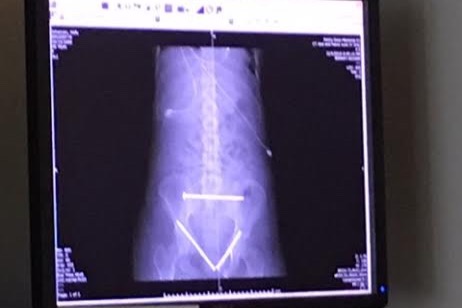

Injury details::: Holly has sustained a number of intense injuries.  She had her spleen removed and surgery on her pelvis which was fractured in half.  She shattered her left hand, broke several ribs and hit her head pretty good.  Her brain is getting better and better everyday, but needs time to heal.  She was in the ICU for over a month and is now home due to insurance issues.  She will be in a wheelchair for at least 3 months and will need assistance everyday for regular tasks.